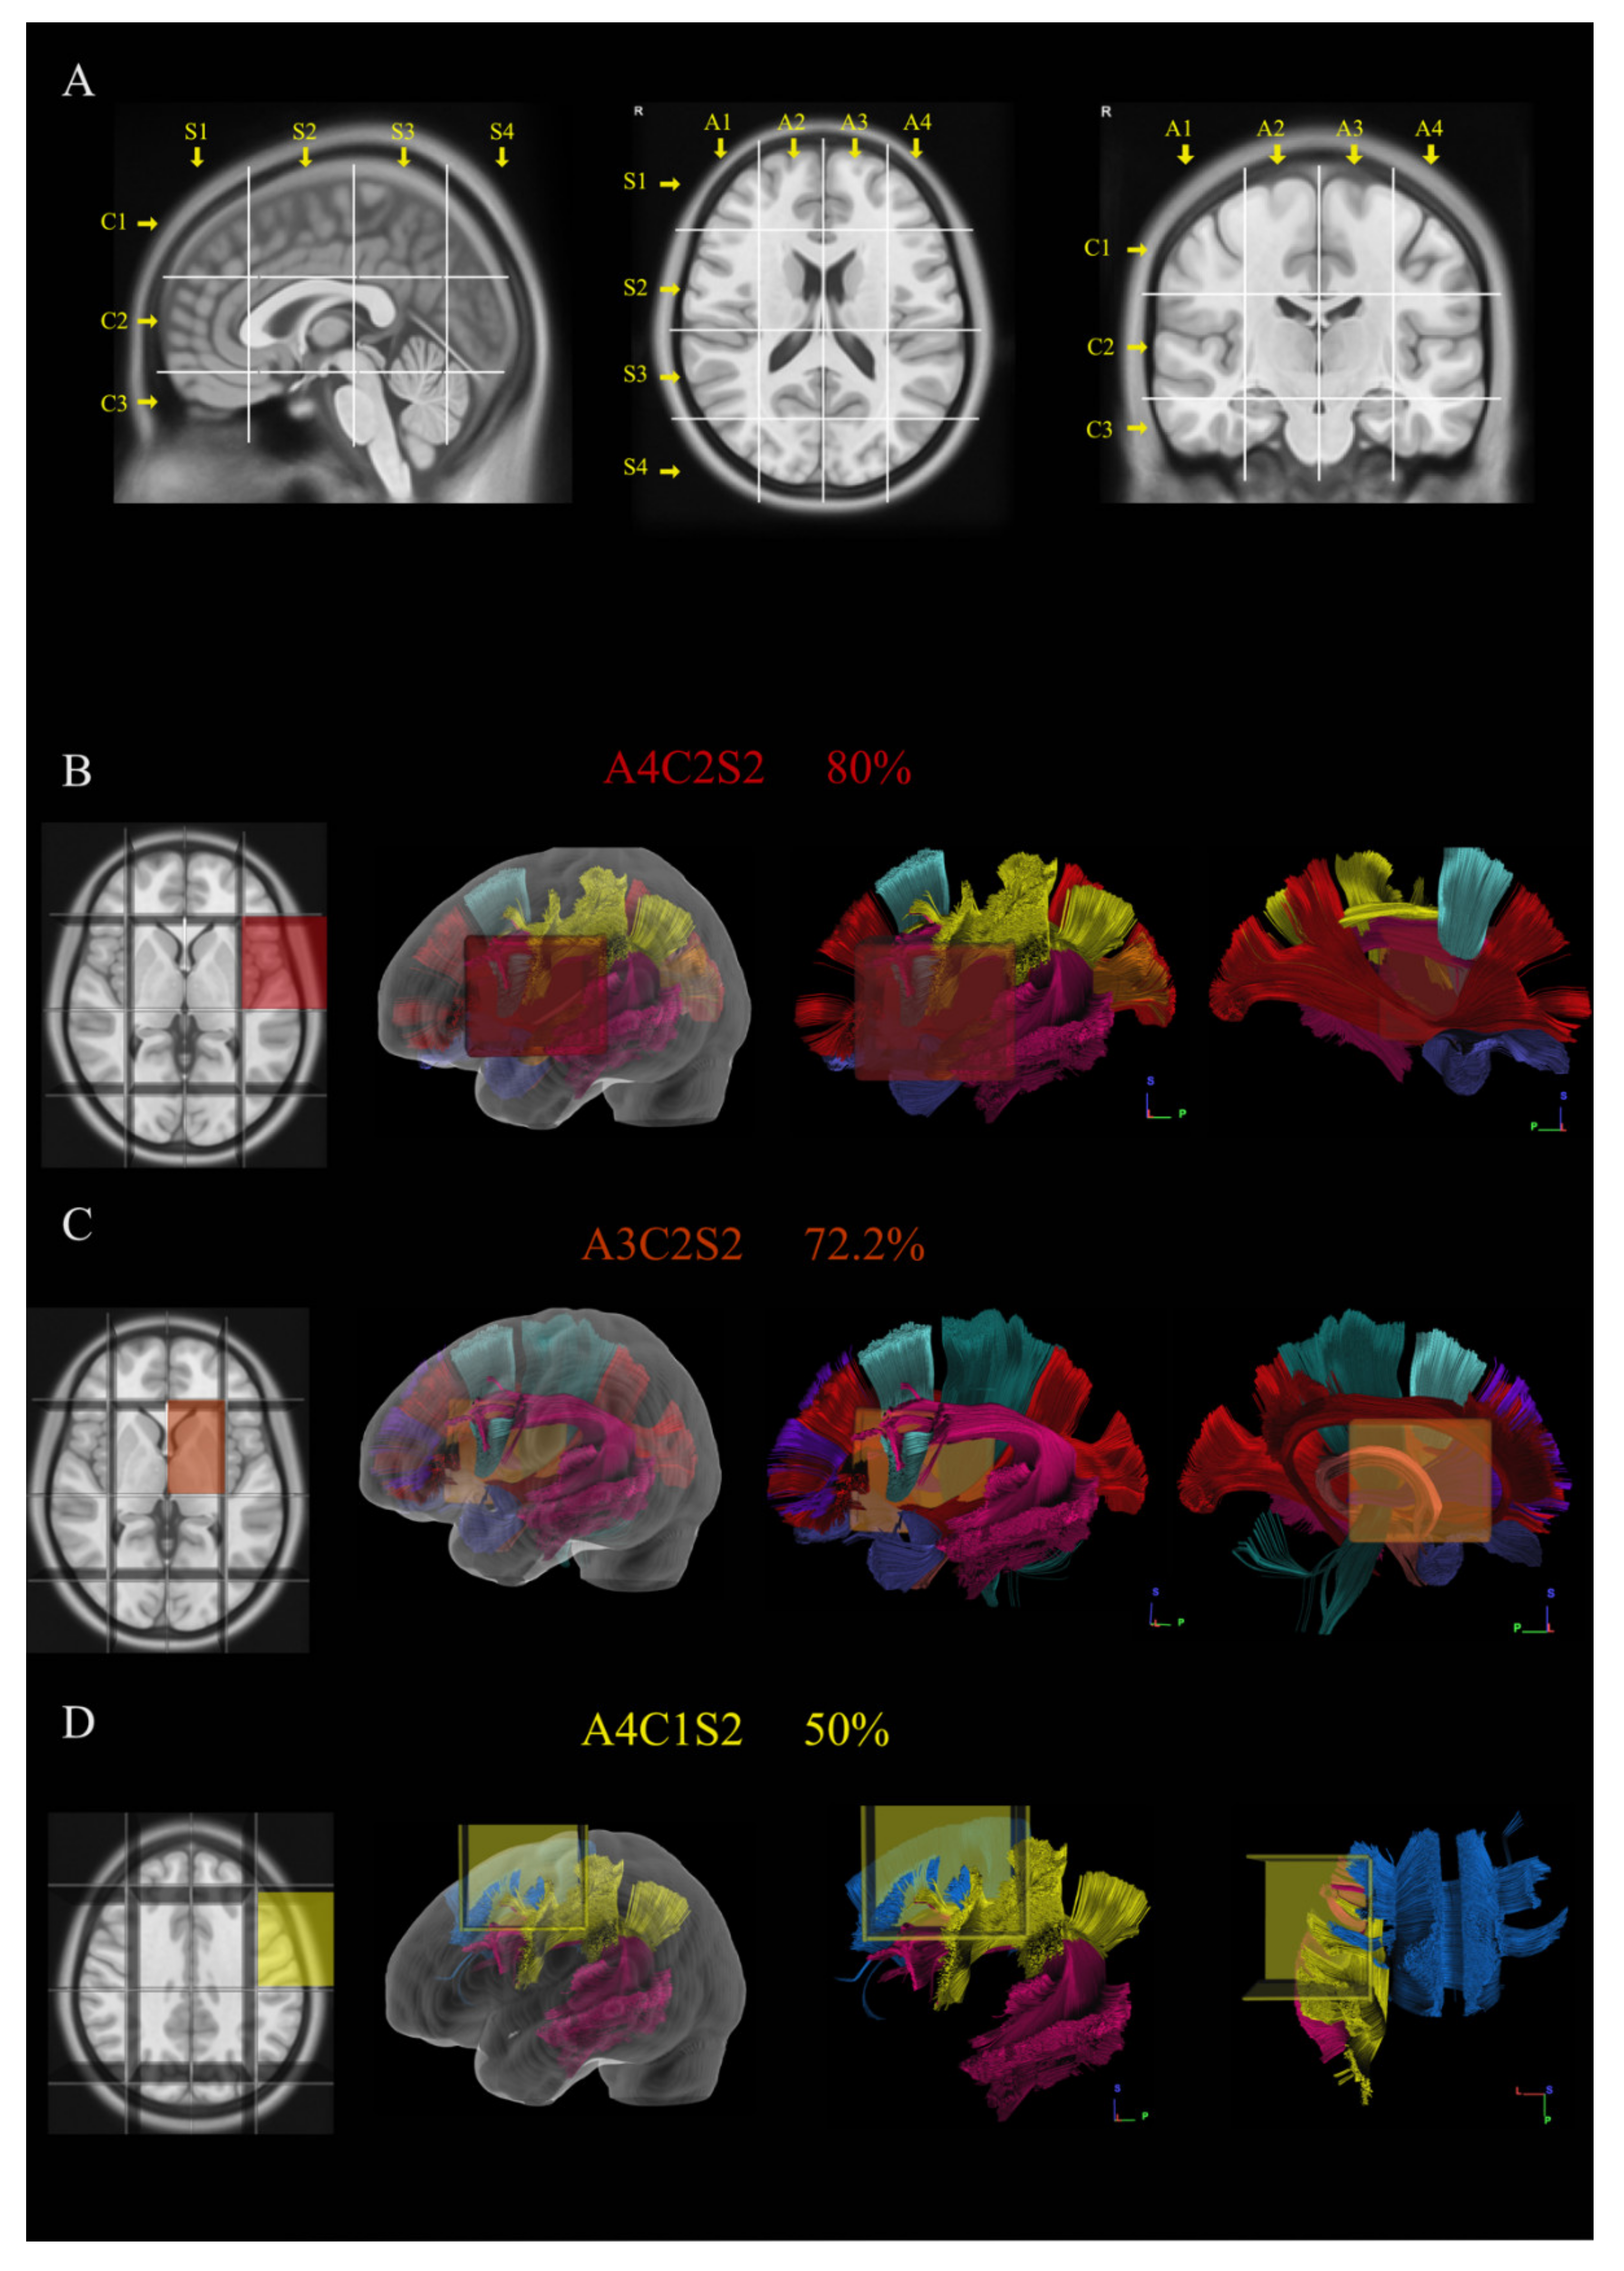

2.3. Brain-Grid Analysis

- Latini, F.; Fahlström, M.; Berntsson, S.G.; Larsson, E.-M.; Smits, A.; Ryttlefors, M. A novel radiological classification system for cerebral gliomas: The Brain-Grid. PLoS ONE 2019, 14, e0211243. [Google Scholar] [CrossRef]

- Latini, F.; Fahlström, M.; Hesselager, G.; Zetterling, M.; Ryttlefors, M. Differences in the preferential location and invasiveness of diffuse low-grade gliomas and their impact on outcome. Cancer Med. 2020, 9, 5446–5458. [Google Scholar] [CrossRef]